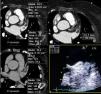

Definição dos parâmetros de avaliação quantitativa da qualidade de imagemO rácio sinal/ruído é obtido por desenho de uma região de interesse no centro da aurícula esquerda e dividindo a densidade média pelo desvio padrão. (Figura 3). Em relação ao rácio contraste/ruído, nesse tipo de exame e tendo em conta a importância de exclusão de trombo, optámos por definir esse parâmetro em relação à densidade do miocárdio do ventrículo esquerdo, e não em relação à gordura epicárdica, uma vez que o miocárdio do ventrículo esquerdo é a estrutura limítrofe com o AAEsq com menor diferença de densidade em relação ao lúmen do mesmo. Para o cálculo desse parâmetro foram desenhadas regiões de interesse no AAEsq (local de menor densidade visual) e intramiocárdico, no segmento do miocárdio em maior proximidade do AAE. O rácio foi obtido da seguinte forma (densidade média do AAEsq – densidade média do miocárdio)/desvio padrão do AAEsq. A homogeneização de densidade entre a AEsq e o AAEsq é obtida pela divisão da densidade média da AEsq obtida na região de interesse desenhada no local visual de maior densidade com a densidade média obtida da região de interesse desenhada no local de menor densidade visual no AAEsq. (Figura 3)

Cálculo dos índices de sinal/ruído e contraste/ruído.

A) Região de interesse (ROI) na AEsq; B) ROI no AAEsq; C) ROI na parede do VEsq.

Cálculo sinal/ruído = Densidade média AEsq/Desvio padrão AEsq.

Cálculo contraste/ruído = (densidade média AAEsq‐densidade média da parede Vesq)/Desvio padrão AAEsq.

Avaliação da homogenização de contraste AEsq/AAEsq = Densidade média AEsq/Densidade média da área de menor densidade no AAEsq.